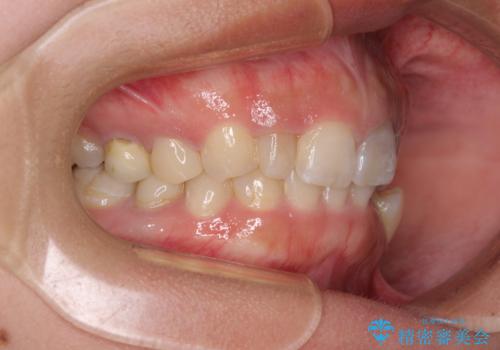

下顎の小臼歯を移動しきるのに2年弱の期間を要することとなり、補綴治療も合わせて2年半ほどの治療期間となりました。

口元の印象が大きく改善し、患者様には大変満足していただけました。